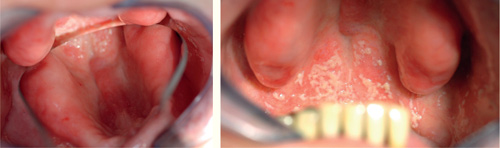

Infeksjoner i munnhulen vil kunne påvirke pasientens generelle helse på mange måter. I første omgang er det ugunstig for pasienten å ha større inflammasjonsprosesser i det hele tatt, fordi dette innebærer at immunforsvaret konstant må jobbe for å holde infeksjonen i sjakk. Dette er spesielt ugunstig for personer som har andre systemiske sykdommer som også krever et immunforsvar i full beredskap, for eksempel pasienter med leddgikt, immunsvekkende sykdommer eller kreft. Økt tilvekst av mikrober i munnhulen gir også økt sannsynlighet for at disse mikrobene kan forårsake infeksjoner andre steder i kroppen. Mikrober kan passere fra munnslimhinnen og over i blodbanen og spres til hele kroppen (3,4,21,28). Dette er spesielt ugunstig for personer med kunstige hjerteklaffer og immunsvekkede pasienter som er mer utsatt for livstruende infeksjoner. Patogene mikrober kan også løsne fra biofilmen i munnhulen og innåndes til lungene. Det blir ofte påvist orale bakterier i lungene hos eldre pasienter som er døde av lungebetennelse (21,28). C. albicans fra munnhulen kan spres til svelget og føre til systemisk soppinfeksjon i hele mage-tarmtraktus, noe som er svært ubehagelig og vanskelig å bekjempe ettersom infeksjonen residiverer raskt etter medikamentell behandling (figur 5) (24,29).

Figur 5. Pasient med protesestomatitt under en gammel helprotese med spredning til svelget. Foto: M. Øilo.